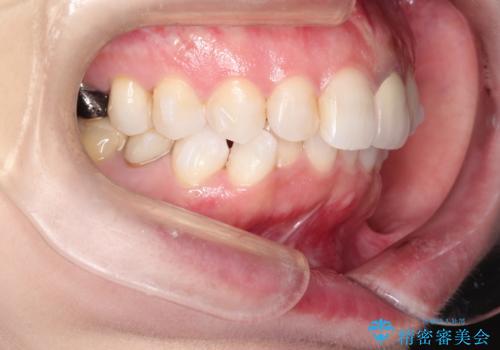

インビザラインによる非抜歯矯正 ガタガタな歯並びを整った歯並びへ

- 上下の全体的ながたつきが気になるとのことで来院されました。

マウスピースでの目立たない矯正を希望されたので、インビザラインでの治療となりました。

全体的に歯と歯の間にわずかに隙間を作り、歯を並べました。